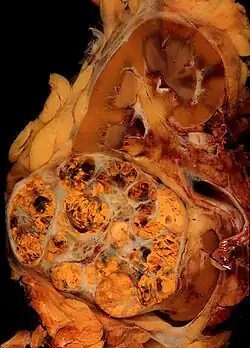

Jest to najczęstszy typ raka nerki i stanowi około 70–80% przypadków[45]. Występuje w korze nerki, najczęściej w pojedynczych ogniskach. Występowanie obustronne lub wieloogniskowe stanowi poniżej 5% przypadków i zwykle wiąże się z predyspozycją dziedziczną (np. zespołem von Hippla-Lindaua)[1]. Makroskopowo guz wielobarwny, żółty do pomarańczowego, często są obecne ogniska martwicy, zmiany krwotoczne, zwapnienia i torbiele[1][46]. Zazwyczaj granice guza są wyraźne[1]. Rozmiar zmiany nie jest wyznacznikiem złośliwości, jednak większy rozmiar guza wiąże się z większym ryzykiem obecności przerzutów[1]. Powiększając się, zajmuje układ kielichowo-miedniczkowy i może wnikać do moczowodu. Stosunkowo często wrasta w żyłę nerkową, sięgając żyły głównej dolnej, a sporadycznie nawet do prawego przedsionka. Przerzuty daje głównie drogą krwionośną poprzez żyłę główną dolną do płuc[1]. Możliwe jest również szerzenie się przerzutów poprzez żyły przykręgosłupowe, żyły jądrowe/jajnikowe, poprzez moczowód i drogą naczyń limfatycznych[1]. Zdarzają się późne przerzuty rozpoznawane nawet po dziesięciu latach choroby[1]. Mikroskopowo nowotwór składa się z komórek o jasnej lub ziarnistej kwasochłonnej cytoplazmie. Jasny wygląd cytoplazmy wynika z nagromadzenia się w niej lipidów i glikogenu, które zostają usunięte na skutek rozpuszczenia w alkoholu podczas rutynowego odwadniania preparatu[1][46]. Jądra są ułożone centralnie; cechują się zróżnicowanym wyglądem i mogą być od małych, drobnych, bez jąderek do dużych, nadbarwliwych i nieregularnych[1]. Podścielisko jest skąpe z siatką cienkościennych naczyń włosowatych, charakterystyczną dla tego typu nowotworu[1]. Komórki tworzą poronne cewki, sznury, wyścielają torbiele lub są chaotycznie ułożone[46].